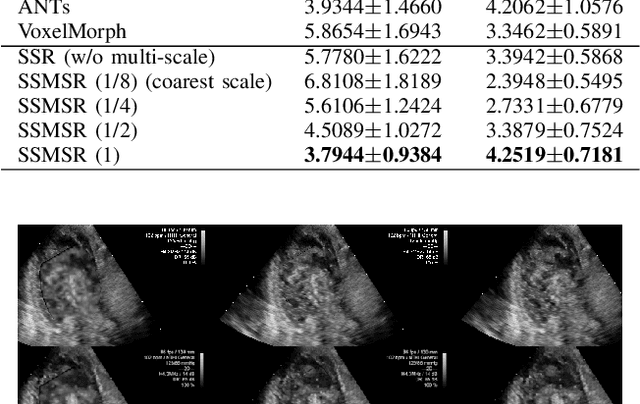

Abstract:Registration is a fundamental task in medical robotics and is often a crucial step for many downstream tasks such as motion analysis, intra-operative tracking and image segmentation. Popular registration methods such as ANTs and NiftyReg optimize objective functions for each pair of images from scratch, which are time-consuming for 3D and sequential images with complex deformations. Recently, deep learning-based registration approaches such as VoxelMorph have been emerging and achieve competitive performance. In this work, we construct a test-time training for deep deformable image registration to improve the generalization ability of conventional learning-based registration model. We design multi-scale deep networks to consecutively model the residual deformations, which is effective for high variational deformations. Extensive experiments validate the effectiveness of multi-scale deep registration with test-time training based on Dice coefficient for image segmentation and mean square error (MSE), normalized local cross-correlation (NLCC) for tissue dense tracking tasks. Two videos are in https://www.youtube.com/watch?v=NvLrCaqCiAE and https://www.youtube.com/watch?v=pEA6ZmtTNuQ